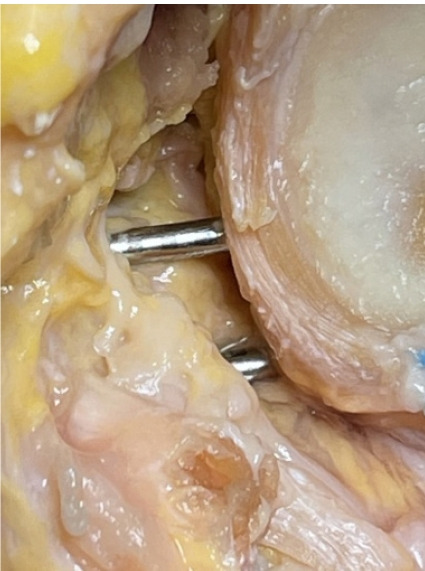

Methods: Anterior glenoid bone block reconstruction with suture buttons utilizing a posteroanterior reference guide was performed in 10 fresh frozen cadavers via a posterior portal. Bullets were inserted in predefined superior and inferior guide holes via percutaneous incisions to facilitate posteroanterior drilling. Looped guide wires were used to deliver suture buttons from anterior to posterior positions. The shoulder joint was disarticulated and the infraspinatus sharply elevated until the suprascapular nerve was visualized. Four independent static measures of the shortest distance from the superior drill sleeve to the lateral aspect of the suprascapular nerve were recorded.